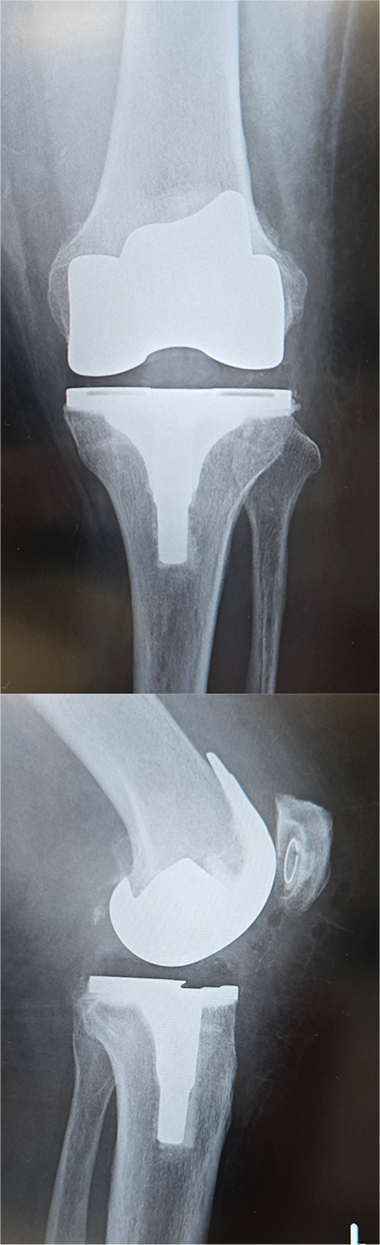

〈手術前のレントゲン〉

〈手術後のレントゲン〉(正面・側面)

右膝

左膝

当院にて人工ひざ関節全置換術(TKA)を施行。両側の手術を同時に行いました。両側同時手術の場合でも入院期間は片側手術の場合と大きく変わらず(プラス1週間程度)、麻酔も1回で済むために身体的、経済的な負担の軽減を期待できます。また両ひざが同程度に悪いケースも少なくなく、同時に行うことで左右のバランスが良くなるためにリハビリをスムーズに進めることが可能となります。

*写真・動画はご本人の承諾を得て掲載しております。(執刀/撮影:森島)

*術後の経過には個人差があります。